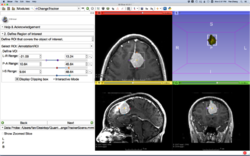

Slicer4 Neurosurgical Planning Tutorial

- The Neurosurgical Planning tutorial course guides through the generation of fiber tracts in the vicinity of a tumor.

- Author: Sonia Pujol, Ph.D., Ron Kikinis, M.D.

- Audience: End-users and developers

- Modules: Volumes, Editor, Tractography Label Map Seeding, Tractography Interactive Seeding

- Based on: 3D Slicer version 4.5

- The White Matter Exploration datasets contains a Diffusion Weighted Imaging scan of brain tumor patient.